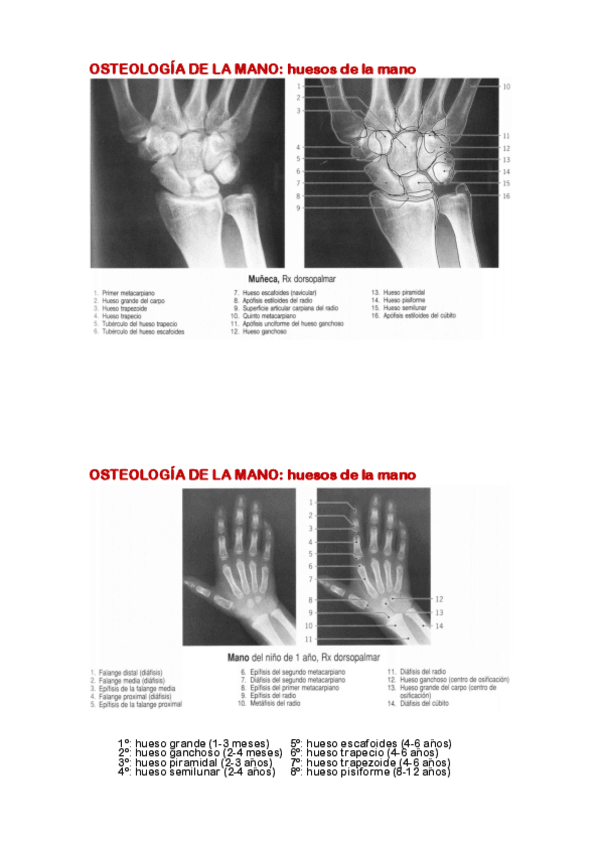

He publicado nuevos apuntes de 1º Anatomía General: SEMINARIO-EXTREMIDAD-SUPERIOR.pdf

14 páginas